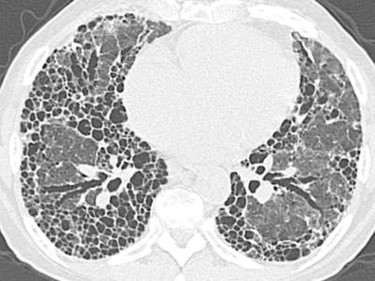

Blickdiagnosen Trockener Husten Belastungsdyspnoe Springermedizin De